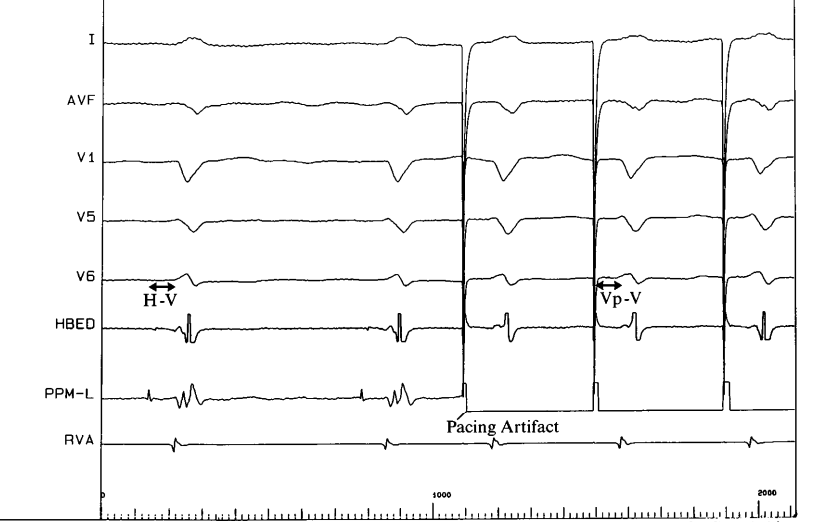

His recording from pacing lead

His.JPG

His capture

His_capture.JPG

LBBB correction at high output

correction_high_output.JPG

Assessing LB capture

• RBBB morphology with unipolar pacing

• LB potential

• LVAT

• V6 to V1 interval